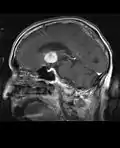

• MRI significantly underestimates extent of involvement; May appear focal on CT or MRI but parenchyma is typically diffusely involved.

• Intensely enhancing on MRI; may have a diffuse or “cotton wool” appearance on imaging.